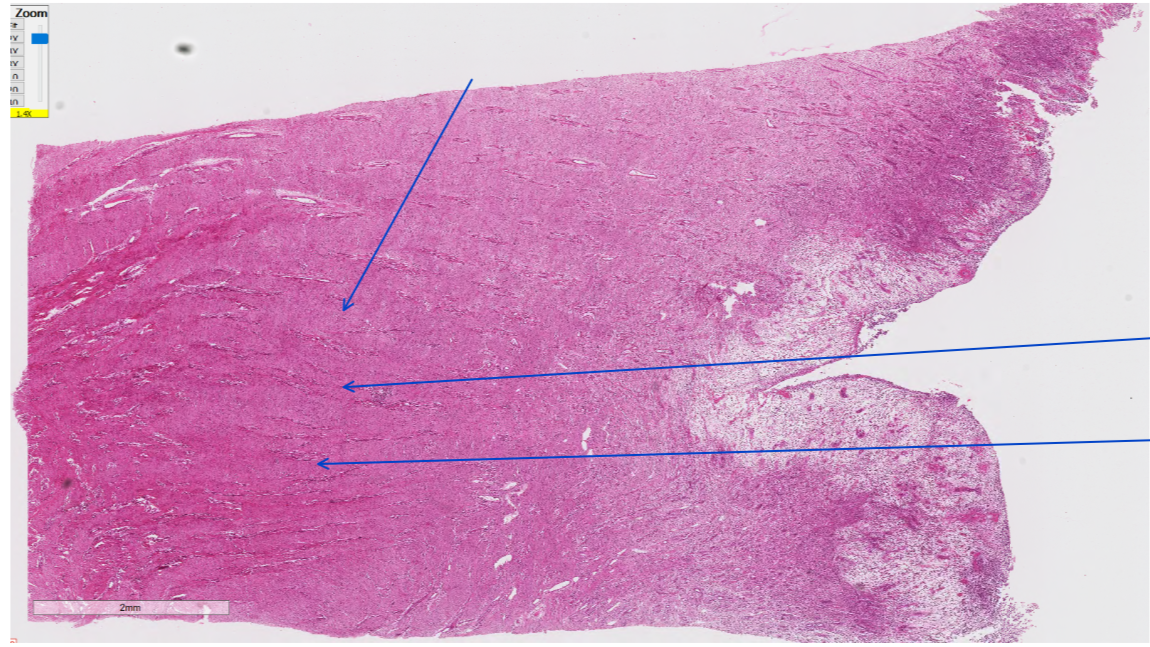

Describe this lesion.

Ribs: Focally and midway between the costocondral junction and head of the 9th rib, there is a smooth, firm mass that is attached to the rib. On cut surface, there is a small, thin fracture line transversing the cortex and medulla of the rib. The fracture is bridged on each side by white, firm tissue that is slightly less rigid than the surround normal bone (fracture callus).

What is the morphological diagnosis of this neoplasm?

focal, transverse, chronic rib fracture with callus formation